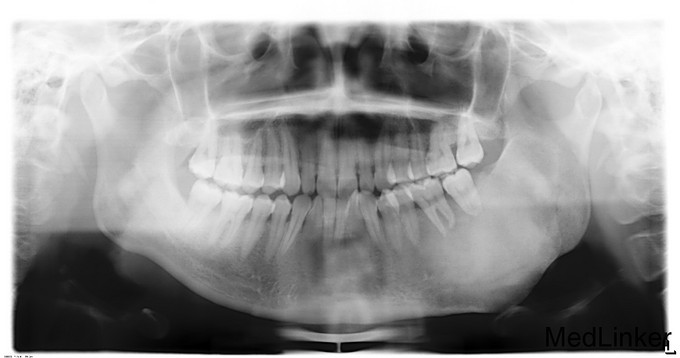

发现左下颌骨局部肿大6年,青年女患者,慢性病程。患者于6年前无明显诱因发现左下颌骨局部肿大,逐渐加重,无明显疼痛、口角麻木等不适。今为进一步治疗来我院就诊,门诊以"左下颌骨骨纤维异常增殖症"收入院

颌面部左右不对称,左下颌区较右侧肥大,开口型正常,开口度4.0cm,双侧关节无明显压痛、弹响,双侧髁突动度左右基本对称。左下颌骨约35至磨牙后区颌骨肿大,前庭沟变浅,同时舌侧可及肿大,质地硬,黏膜无破溃流脓,牙齿无明显松动。

诊断:左下颌骨骨纤维异样增殖症,全麻下行“左下颌骨整形行性切除+左下颌角修整术+邻近瓣转移修复术”